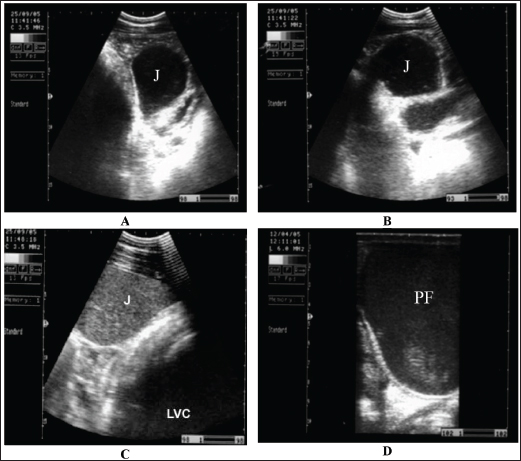

Fig. 9. Sonogram of horses with obstructive colic: (A) jejunum (J) imaged in the left ventral abdomen using a 3.5-MHz transducer. The greatly distended loop of the jejunum and its contents are of mixed echogenicity. (B) Image of jejunum in left ventral abdomen using a 3.5-MHz transducer. The greatly distended loop of the jejunum and its contents are of mixed echogenicity. (C) The jejunum and left ventral colon are obtained from the left flank region caudal to the costal arch. The jejunal contents were more echogenic. The left ventral colon shows no sacculations. (D) Pelvic flexure (PF) obtained from the transrectal window using a 6-MHz transducer. It appears that complete ileus was observed during real-time scanning.